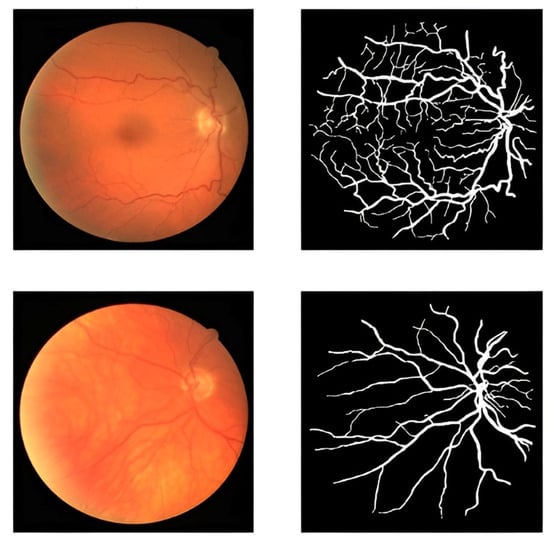

3.1. DRIVE Dataset

4.3. Results of Data Augmentation Layer

4.4. Results of Segmentation Stage